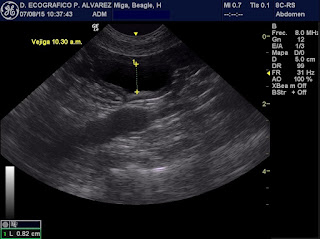

La ecografía abdominal revela unos riñones de tamaño normal y simétricos, pero con una marcadísima hiperecogenicidad de la corteza renal. No se observan signos de pielectasia ni derrame perinéfrico. La vejiga de la orina presenta casi nula distensión (en este momento se vuelve a interrogar a los propietarios, los cuales confirman que Miga no ha orinado desde el día anterior).

Se procede entonces a realizar un protocolo de diuresis forzada, inicialmente con furosemida (dos dosis) y posteriormente con manitol en CRI, valorándose la producción de orina a lo largo del tiempo midiendo el grosor de la luz vesical tomando el mismo corte ecográfico a igual profundidad y aumento.